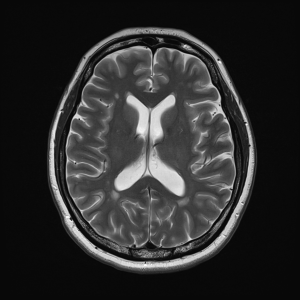

This imaging technique provides a non-invasive look inside the brain using powerful magnetic resonance technology. It is particularly beneficial for individuals with stroke risk factors.